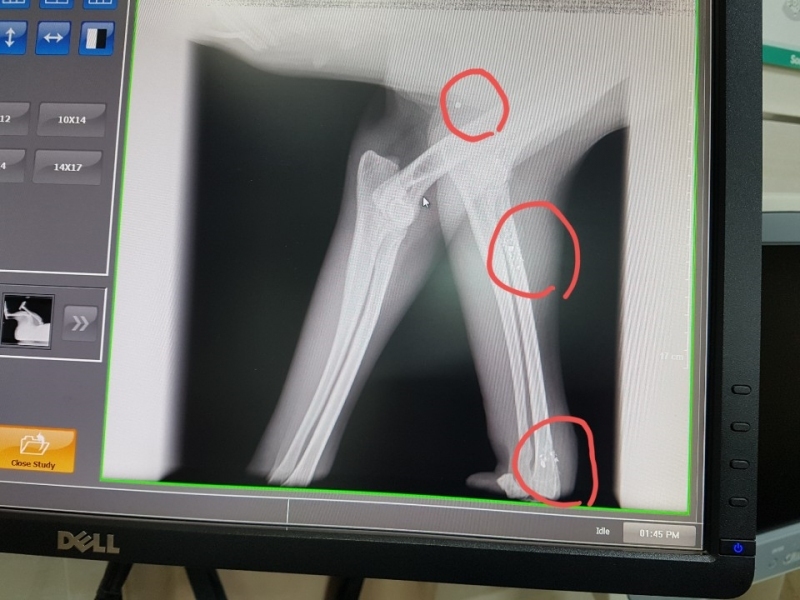

¿À´Ã ¼º³²¿¡ Àִ µ¿¹°º´¿ø¿¡ °¡¼­ ¿¢½º·¹À̸¦ Âï¾îº» °á°ú

½ÇźÀÌ ¿©·¯¹ß ¹ÚÇôÀִµ¥  ¼ö¼úÀ» ¸øÇÏ°í ¸Ô´Â°ÍÀº Àß ¸ÔÀ¸´Ï

°ßÀÌ ¸Ô´Â°Íµµ À߸԰í Ȱ¹ßÇѵ¥  ¿ÞÂÊ ¹ß¸ñÀ» ¾²Áö ¸øÇÕ´Ï´Ù,

¿ÞÂÊ´Ù¸® ¹ß¸ñ¿¡ ½ÇźÀÌ ¹ÚÇôÀִµ¥ »À¸¦ ¸Â°í ½ÇźÀÌ ºÎ¼­Áø ´À³¦ÀÔ´Ï´Ù,

±×ÂÊÀº Àε¥°¡ Àִµ¥  Àε¥°¡ ²÷¾îÁø°Í  °°¾Æ¿ä,

2¿ù 15ÀÏ ±¤Áֽà ÃÊ¿ù¸é¿¡ ÀÖ´Â À̼ٵ¿¹° º´¿ø¿¡¼­ Á¤¹Ð ¿¢½º·¹ÀÌ ÃÔ¿µ ÇßÀ¾´Ï´Ù,

´Ù¸®¿¡ ºÎ¼­Áø ¿±ÅºÀº »À¿¡ ¸Â¾Æ »À°¡ ±ÝÀ̰¡°í ¾à°£Àº »À¼ÓÀ¸·Î µé¾î °¬´Âµ¥

ºÎ¼­Áø ¿±ÅºÀ» »©´Â ¼ö¼úÀº ºÒ°¡´ÉÇÏ°í µ¿¹°Àº »ç¶÷ÇÏ°í ´Þ¸® ÀÌ»óÇÑ ¹°Ã¼°¡ µé¾î¿À¸é

Ç×ü°¡ »ý°Ü¼­ ¹°Ã¼¸¦ ¿¡¿ö½×°í ¸·ÀÌ »ý°Ü  ´õ´Â ÀÌ»óÀÌ ¾ø°í »ç´Âµ¥´Â ÁöÀåÀÌ ¾ø´Ù°í ÇϽôõ±º¿ä.

¿±ÅºÀÌ ½ÉÀå, Æó, ³»Àå±îÁö µé¾î°¡¸é À§ÇèÇѵ¥ ¸ö¼Ó¿¡ ¹ÛÈù°ÍÀº

¸Ô±â¸¸ ÀßÇÏ¸é »ì¼ö ÀÖ°í 3ÁÖ ÈÄ¿£ °ÅÀÇ Á¤»ó±îÁö ¿À´Ï±î ½Ã°£À» °¡Áö°í

±â´Ù·Á º¸¶ó´Â  µ¿¹°º´¿ø¿øÀå´ÔÀÇ Á¾ÇÕÀûÀÎ ÆÇ´ÜÀÔ´Ï´Ù,